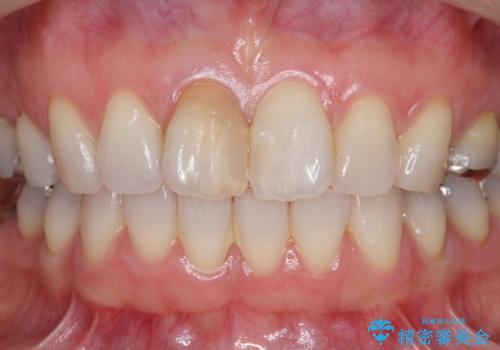

前歯の変色 セラミック審美補綴

以前に神経が死に、根管治療を行った歯の変色が認められたためセラミックによる審美補綴治療を計画します。

- 16万円(仮歯・ファイバーコア・ジルコニアクラウンスペシャル)費用は治療当時の料金となります

神経治療を行い補綴(かぶせもの)治療を行わないと、変色が目立ち審美障害を起こすことがあります。

このような場合、セラミックによる審美改善が治療の一案として提案されます。